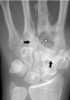

Bone grafting is a surgical procedure that replaces missing bone in order to repair bone fractures that are extremely complex, pose a significant health risk to the patient, or fail to heal properly. Some small or acute fractures can be cured without bone grafting, but the risk is greater for large fractures like compound fractures. [Source: Wikipedia ]